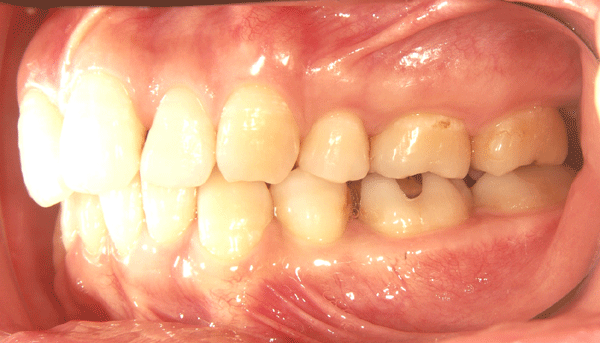

術前の状態

2006.2.18 |